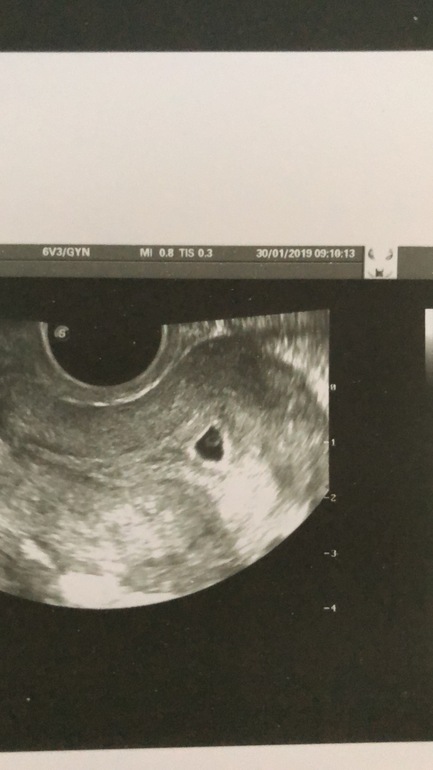

Сходила на узи… даже не знаю расстроилась или нет, по месячным с 19.12.18 получается 6 недель, по узи сказали всего 5 недель, это что значит плохо развивается?